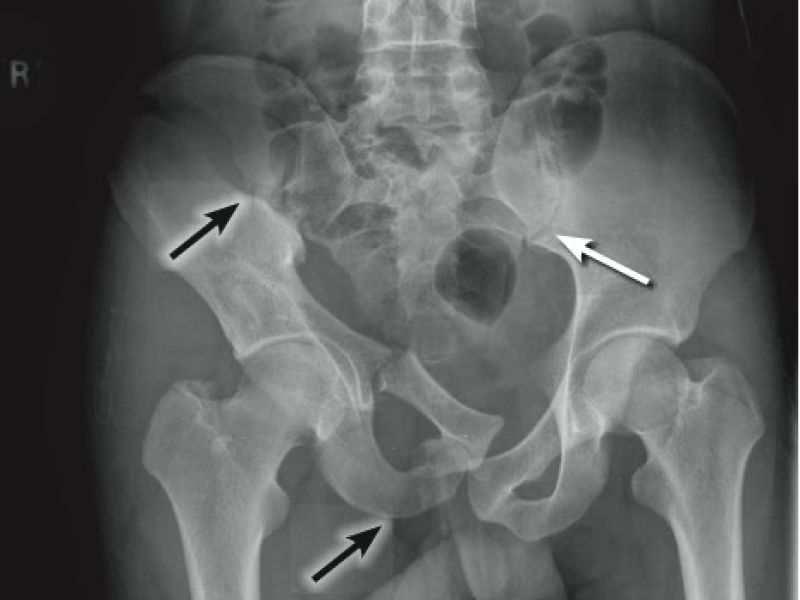

Un estudio publicado recientemente en la revista Advances in Orthopedics reveló que los pacientes con pérdida de sangre de menos de 400 ml tenían 13 veces menos probabilidades de recibir sangre autóloga, y los pacientes con hemoglobina inferior a 10,5 tenían 5 veces menos probabilidades de recibir una transfusión autóloga (p < 0,05) y que ningún paciente con un nivel de hemoglobina inferior a 10,5 y EBL inferior a 400 mL recibió retorno de sangre autóloga.

La transfusión de sangre autóloga no tuvo efecto sobre el volumen o la velocidad de la transfusión de sangre alogénica. Pensamos que si la hemoglobina preoperatoria de un paciente es inferior a 10,5 o si la pérdida de sangre esperada es inferior a 400 mL, entonces la CS debería tener un papel muy limitado, si es que lo tiene, en la estrategia de conservación de sangre preoperatoria. Encontramos un ASA superior a 2, un IMC superior a 24 y el tipo de fractura asociado como un factor de riesgo para la pérdida elevada de sangre.